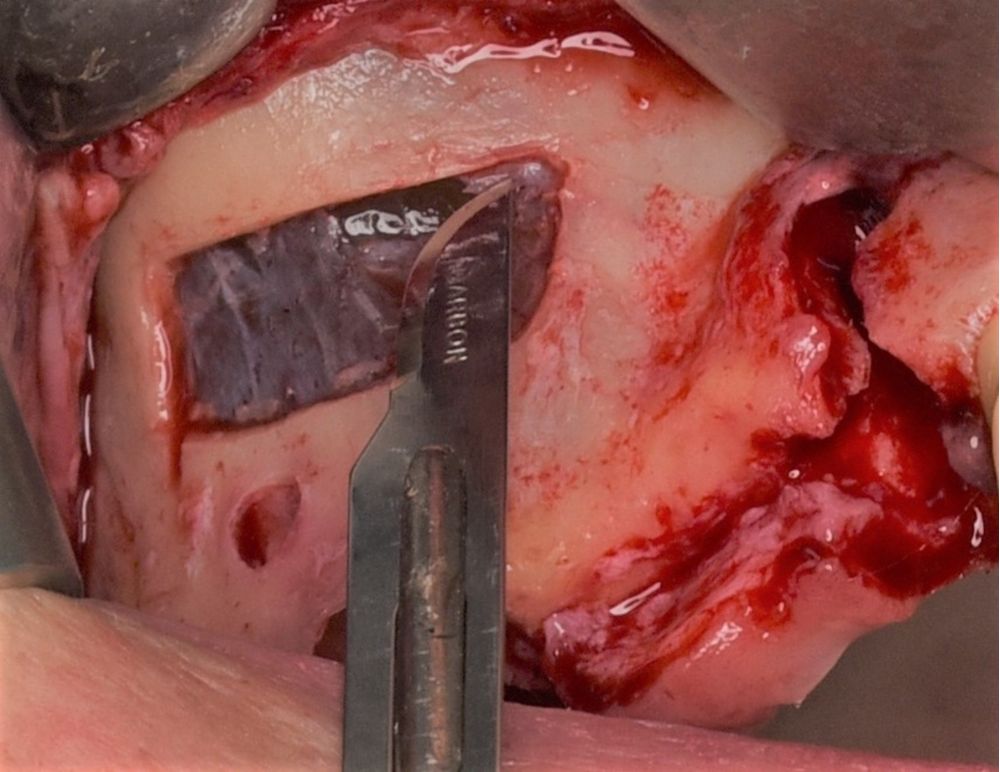

La ostectomía de acceso al seno maxilar en la pared anterior y lateral del seno maxilar de 2.5×0,8 cm se realizó con bisturí piezoeléctrico con inserto de osteotomía de diamante no dentado y abundante irrigación con suero salino (Figura 6). A continuación, se despegó la cortical y se sumergió en suero fisiológico hasta el final de la intervención (Figura 7). Se procedió a incidir la mucosa de Schneider en la zona más superior de la ventana, de mesial a distal en toda la anchura de la ostectomía, hasta penetrar en la luz del pseudoquiste (Figuras 8 y 9). Se realizó el aspirado del contenido del pseudoquiste y el epitelio del pseudoquiste se retiró cuidadosamente con una cucharilla de legrado y curetas de elevación (Figuras 10 y 11). Posteriormente, se desinfectó la cavidad con povidona yodada e irrigación con abundante suero salino. Una vez eliminado el pseudoquiste se procedió al despegamiento de la membrana de Schneider según la técnica habitual de elevación de seno maxilar abierta (Figura 12). Tras comprobar un correcto despegamiento de la membrana de Schneider se realizaron dos perforaciones con bisturí piezoeléctrico e inserto de bola de 3 mm craneales al límite superior de la ostectomía inicial (Figura 13). Se suturó la mucosa de Schneider a estas perforaciones mediante puntos simples con sutura reabsorbible 4/0 (Novosyn quick®) (Figura 14). Se colocó en el interior de la cavidad, en la zona superior, una membrana reabsorbible de colágeno (Geitlisch Bio-Guide®) que se dejó sobresalir de la cavidad hacia el exterior 1 cm (Figura 15). Se procedió al relleno de la cavidad con xenoinjerto (Geitlisch Bio-Oss® de gránulo grueso 1-2 mm) (Figura 16). La tapa de cortical que se había extraído tras la ostectomía se reposicionó y se cubrió con la membrana de colágeno que se había dejado expuesta en la zona superior (Figuras 17 y 18). Finalmente, se reposicionó el colgajo y se suturó con sutura de nylon 5/0 monofilamento no absorbible (Figura 19).